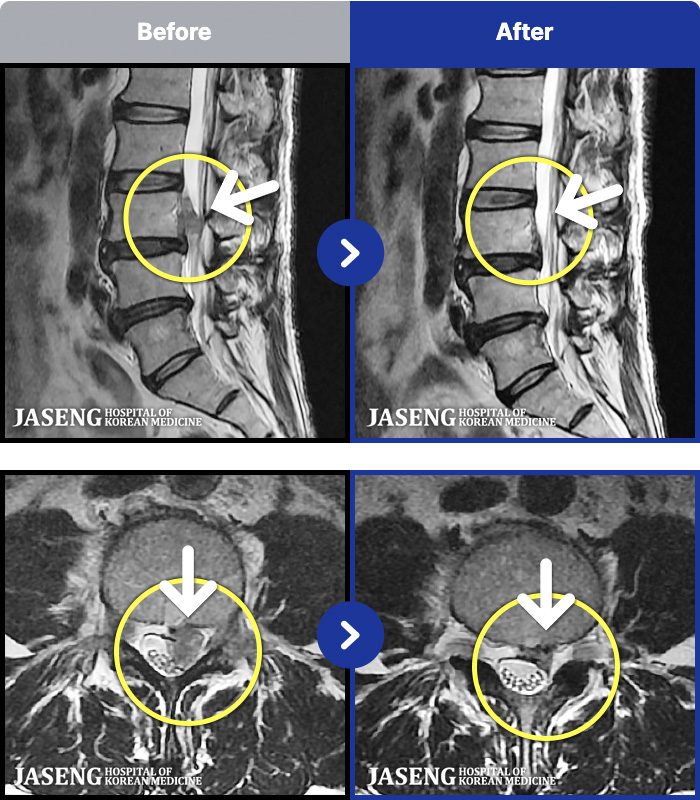

ȯںп Ǹ ǿ ԿǾ, ο ġ ۿ Ƿ ġḦ Ͻñ ٶϴ.